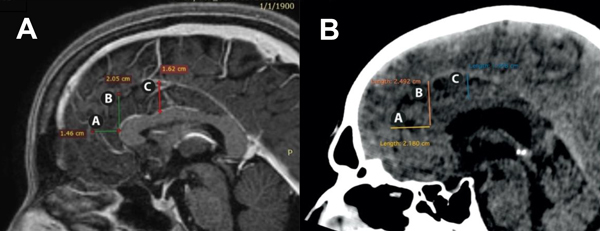

Las mediciones se realizaron en cortes sagitales en RM (Philips Achieva de 1.5T con los siguientes parámetros de adquisición de las imágenes de la secuencia 3D T1: TR = 7ms, TE = 3ms, ángulo de inclinación = 8, matriz de adquisición = 256x222, espesor de corte = 1 mm, tamaño de vóxel = 1x1x1 mm) y TC (Toshiba Lightning 16 Achilles con cortes finos de 0,5 mm) de cerebros normales (Figura 2). Las mediciones fueron realizadas siempre por las mismas personas y siempre con la misma angulación de los cortes, para evitar sesgos.

Figura 2:

A: Distancias A, B y C en resonancia magnética en plano sagital.

B: Distancias A, B y C en tomografía computarizada en plano sagital